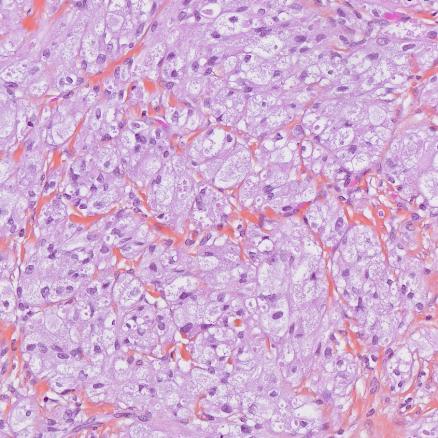

Le diagnostic formel repose sur l’histologie : cellules polygonales à cytoplasme granuleux éosinophile, à coloration PAS (Periodic Acid Schiff) positive (fig. 2). L’immuno-histochimie est caractéristique.